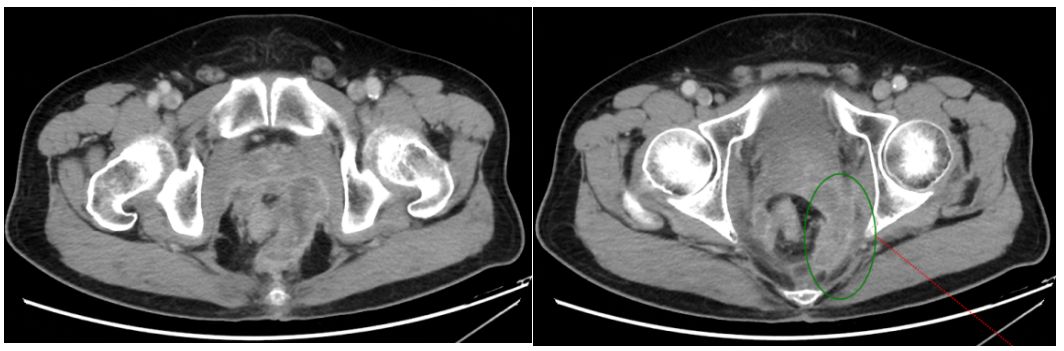

2020年11月20日,再次腹盆腔CT增强:“直肠癌术后+前腹壁造瘘术”后改变,局段直肠壁增厚伴邻近筋膜增厚、腹膜反折处结节样增厚,需考虑肿瘤复发可能,较前片(2020年9月7日)略有进展,较前片(2020年4月10日)明显进展。疗效评估为疾病进展(PD)。

2020年11月21日至今,予三线靶向呋喹替尼联合信迪利单抗免疫治疗,具体方案:呋喹替尼(3mg po d1-14)+信迪利单抗(200mg d1,q21d)。

2021年5月13日开始每3个月复查1次,疗效评估均为持续PR。